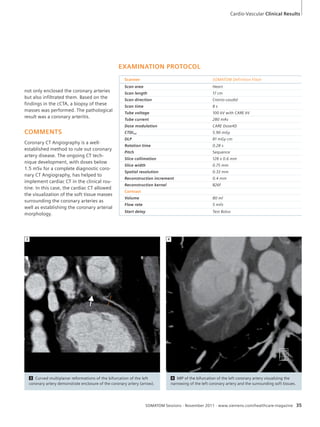

Cardio-Vascular

34 SOMATOM Definition Flash: Ruling

out Coronary Artery Disease and

Diagnosing Coronary Arteritis with

1.3 mSv